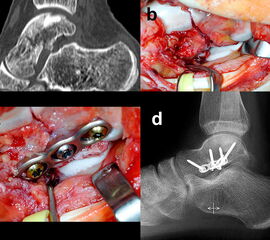

Verbleibt nach der Versorgung aller knöchernen Verletzungen eine ligamentäre Instabilität, so ist zur sicheren Bandheilung und damit auch Protektion der Osteosynthese eine temporäre Gelenktransfixierung für 6 Wochen indiziert 5. Dies betrifft nach der Versorgung von Talushals- und –korpusfrakturen eher das Subtalar-Gelenk (Abb. 10), nach Taluskopffrakturen eher das Chopart-Gelenk 12.

Die Zugänge zu dislozierten Taluskorpusfrakturen entsprechen im Wesentlichen denen bei Talushalsfraktur. Bei weit in den zentralen und hinteren Taluskorpus hineinreichenden Frakturen kann zur ausreichenden Übersicht und verbesserten Fragmentmanipulation eine Innenknöchelosteotomie erforderlich werden, sofern der Innenknöchel nicht ohnehin mit frakturiert ist 4. Hierzu wird der anteromediale Zugang nach proximal erweitert. Die Schraubenkanäle werden vorgeborht um eine exakte Refixierung des Innenknöchels nach der Talusosteosynthese zu gewährleisten. Die Osteotomie wird schräg auf den medialen Gelenkwinkel geführt, im eigenen Vorgehen zur besseren Stabilisierung vorzugsweise als Chevron-Osteotomie. Das Subtalargelenk ist bei Taluskorpusfrakturen regelhaft frakturiert und disloziert (Abb. 11). Zur Reposition und Überprüfung der Gelenkkongruenz im Subtalargelenk wird ein zusätzlicher anterolateraler Zugang benötigt.

Das Behandlungskonzept sollte prinzipiell so konzipiert und umsetzbar sein, dass bei einer übungsstabilen Osteosynthese eine frühfunktionelle Behandlung begonnen werden kann. Eine Ausnahme stellen hochgradig instabile Frakturen oder Luxationsfrakturen dar, welche zusätzlich zur Osteosynthese eine temporäre Gelenktransfixierung benötigen 5. Diese erfolgt, falls erforderlich, mit Kirschnerdrähten für 6 Wochen, um eine stabile Bandheilung und eine erste Konsolidierung der Fraktur zu gewährleisten (s. Abb. 10).